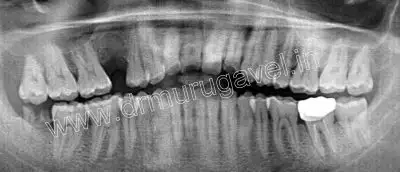

Radiographic examination

Sufficient bone height and width was present in relation to 15 region for placing dental implant.